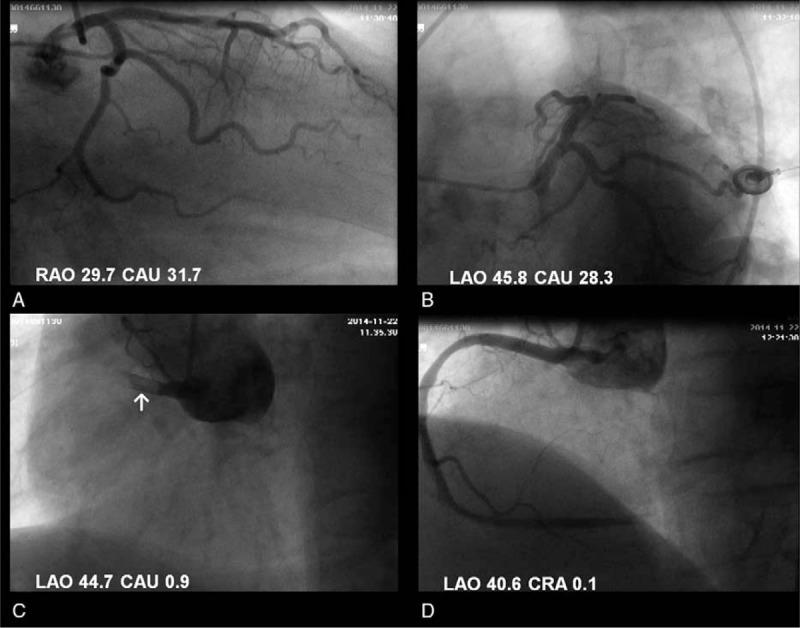

We described a 59-year-old man who presented to emergency department complaining of chest pain.

He was suffered acute myocardial infarction (MI) and pulmonary embolism (PE) simultaneously.

Dual antiplatelet therapy, statin, and low molecular weight heparin were administrated during his stay. The searches for cancers, autoimmune diseases, and hematologic diseases were unremarkable, ruling out a hypercoagulable state. Subsequent ultrasound scan revealed a thrombus in a vein of the lower left extremity. Thus, paradoxical embolism was highly suspected.

Paradoxical embolism is a rare cause of acute MI, which may have occurred in our patient. This was evidenced by a previously unrecognized patent foramen ovale (PFO) with a right-to-left atrial shunt detected using contrast transesophageal echocardiography.

我们描述了一名59岁男性,他因胸痛到急诊科就诊。

他同时患有急性心肌梗死(MI)和肺栓塞(PE)。

住院期间给予双联抗血小板治疗、他汀类药物和低分子肝素。对癌症、自身免疫性疾病和血液系统疾病的检查未发现异常,排除了高凝状态。随后的超声扫描显示左下肢静脉有血栓。因此,高度怀疑为反常栓塞。

反常栓塞是急性心肌梗死的罕见原因,可能在我们的患者中发生。经食管对比超声心动图检测到先前未被识别的卵圆孔未闭(PFO)伴右向左心房分流,证明了这一点。